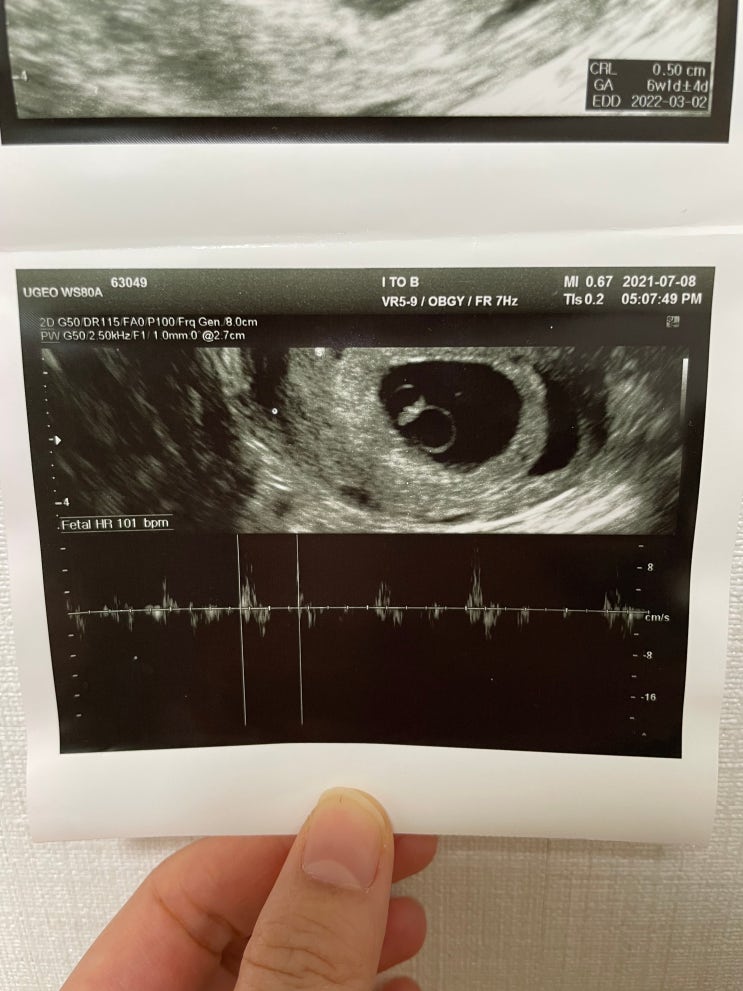

[계류유산] 1년간 두 번의 심정지 계류유산

안녕하세요 이웃 여러분! 굉장히 오랜만에 블로그에 글을 쓰네요 참 많은 일이 있었고 제 마음을 돌보는 시...